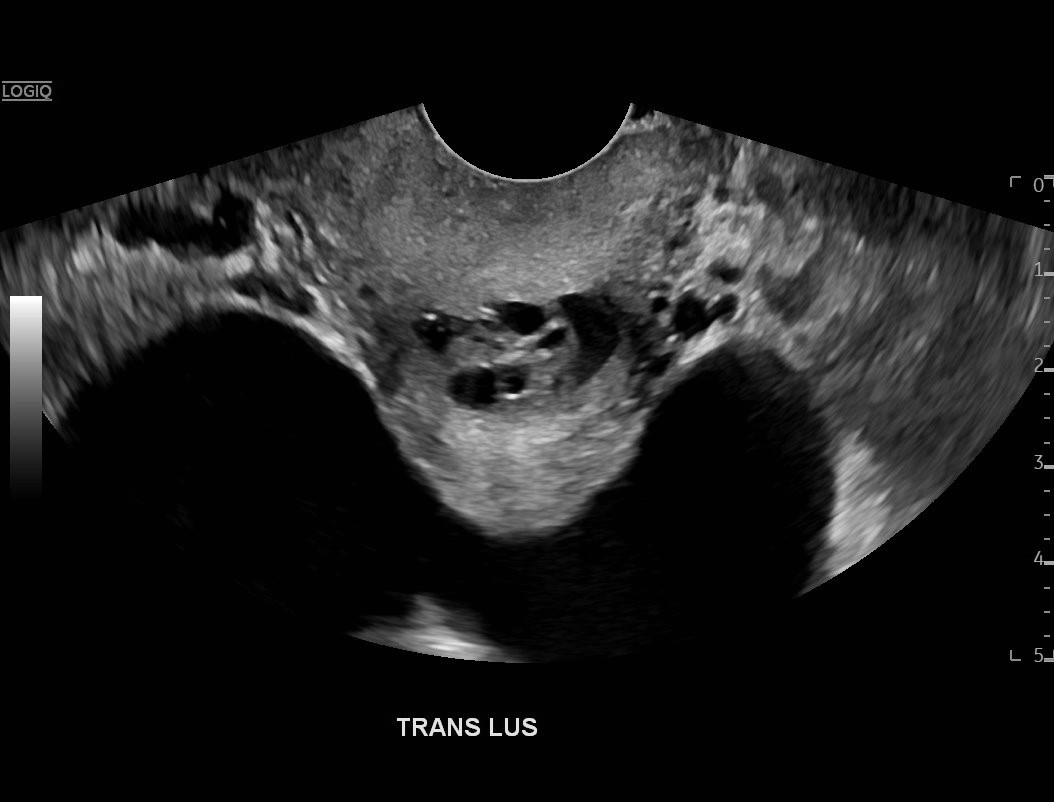

Ovarian hyperstimulation syndrome (OHSS) is a potentially life-threatening complication of assisted reproductive technology (ART). Here, we present the case report of a 30-year-old female undergoing infertility treatment who presented to the emergency department (ED) with nausea and vomiting, abdominal distention, and shortness of breath. On physical exam, she had notable ascites. Computed tomography (CT) of the abdomen and pelvis and pelvic ultrasound (US) revealed significant ascites and enlarged ovaries with multiple cysts. She was diagnosed with severe OHSS and admitted to obstetrics and gynecology (OBGYN) service for five days where she underwent intravenous (IV) hydration and paracentesis. This case report reviews the clinical presentation, categorization, management, and prevention of OHSS and provides examples of imaging findings consistent with the condition.